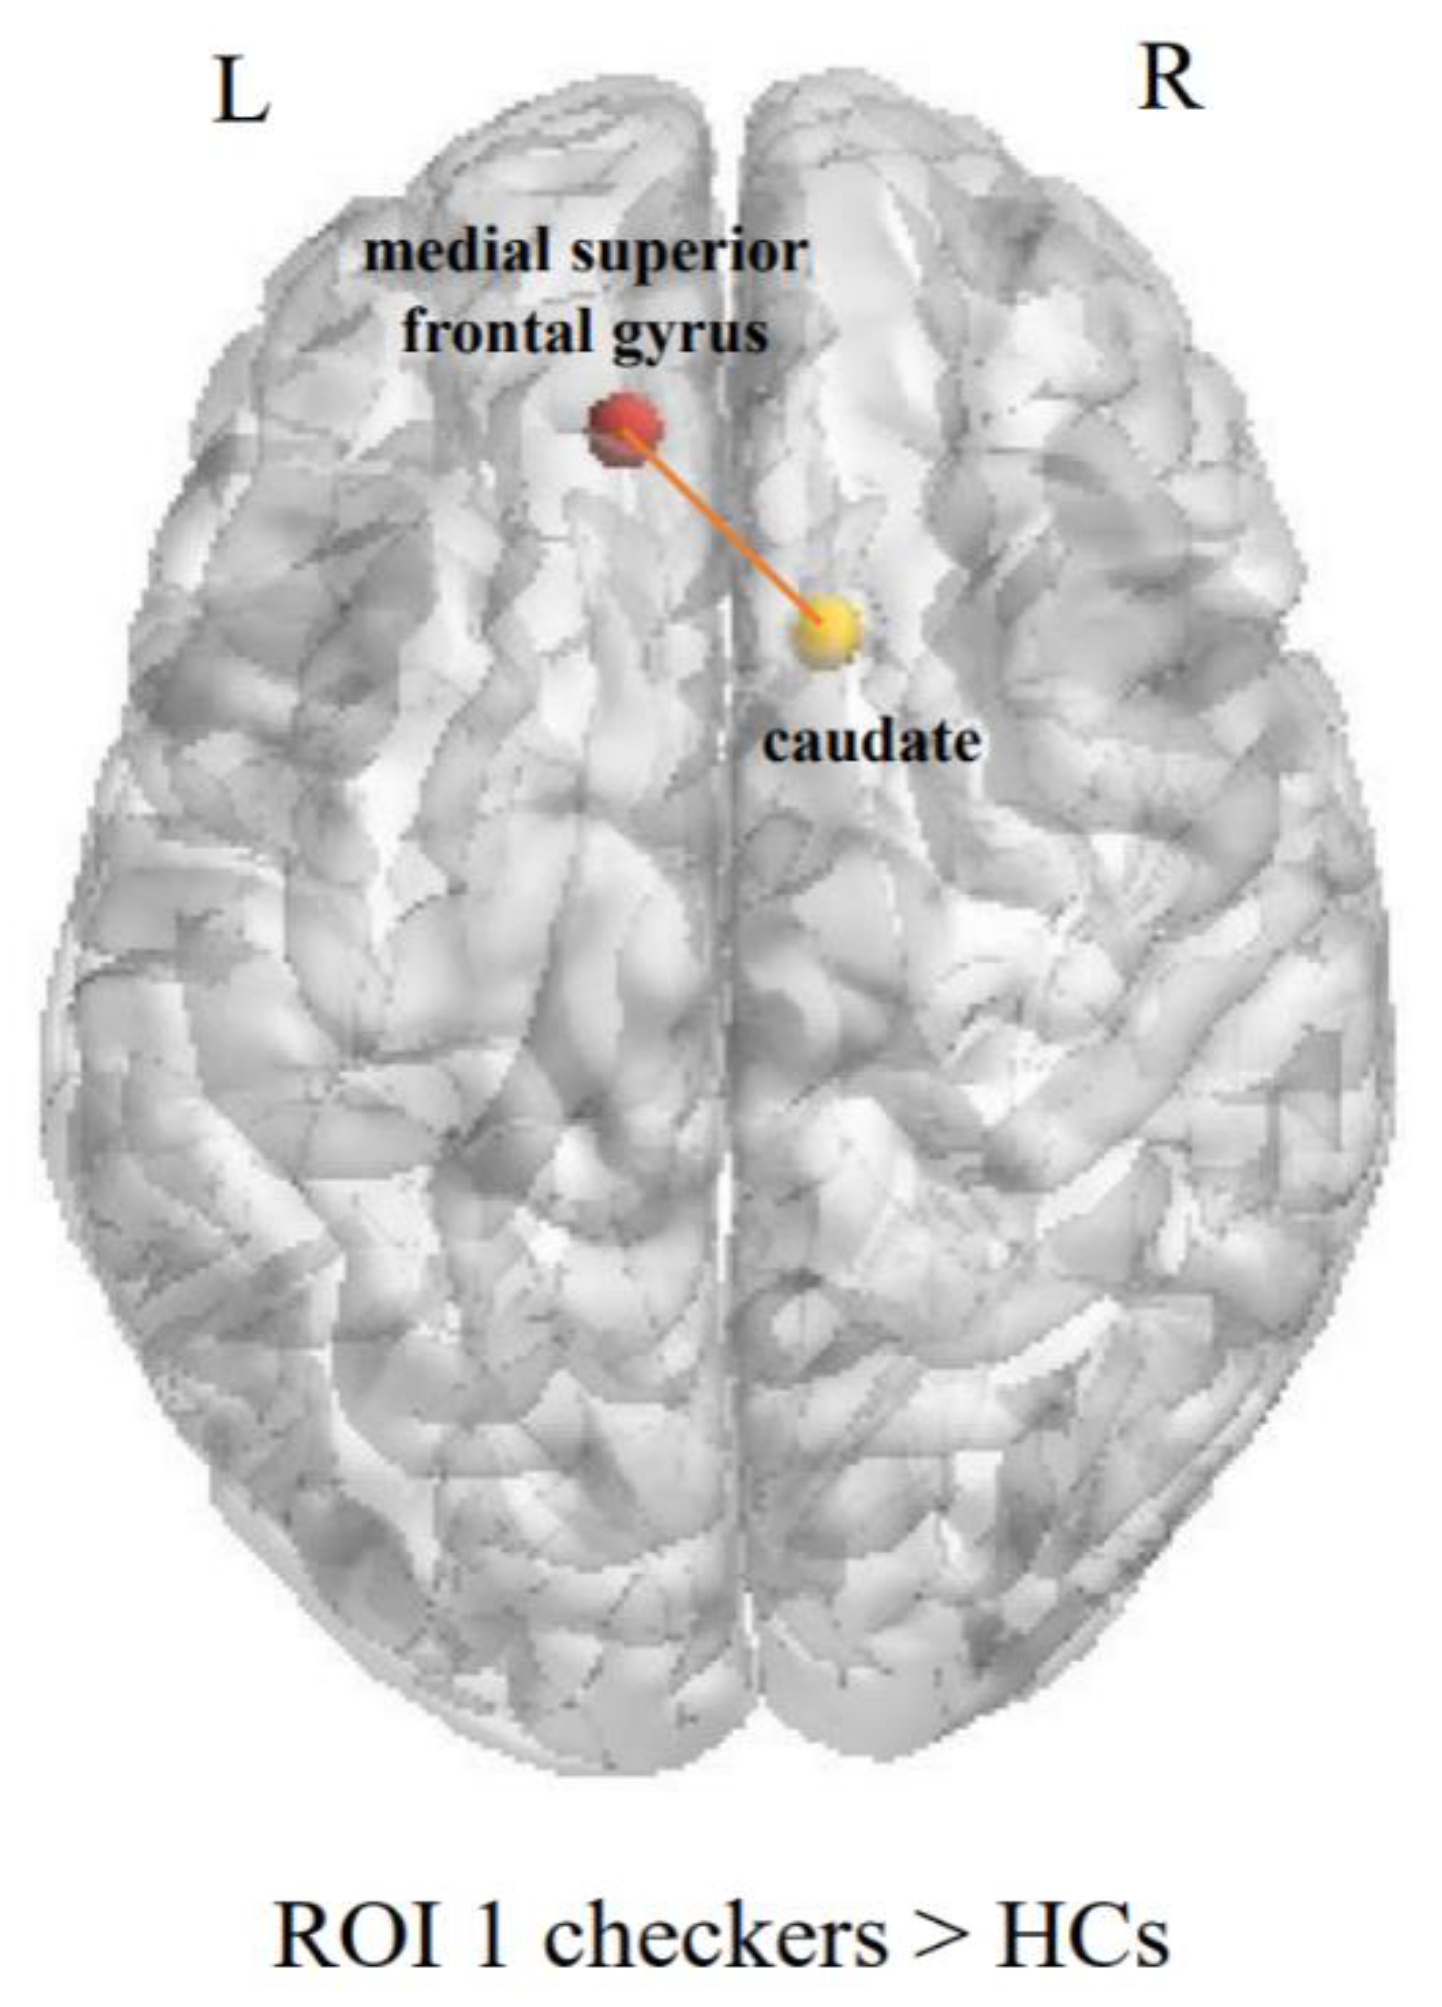

| Checkers vs. HCs | Frontal_Sup_Medial_L | 0.829 | 0.9768 | 80% (24/30) | 80% (36/45) |

| Precuneus_L | 0.764 | 1.1370 | 73.3% (22/30) | 68.9% (31/45) | |

| Seeds | Group | MNI x, y, z | Voxels | T Values | Side | Brain Region |

|---|---|---|---|---|---|---|

| Frontal_Sup_Medial_L | Checkers > HCs | 12, 15, 15 | 14 | 13.1601 | R | caudate |

| Precuneus_L | - | - | - | - | - | - |

| ROI 1- | Right caudate | −0.038 (0.842) | 0.095 (0.616) | −0.051 (0.790) | −0.138 (0.492) | −0.206 (0.303) | −0.100 (0.621) | 0.025 (0.900) | −0.092 (0.648) | −0.263 (0.184) | −0.028 (0.888) |